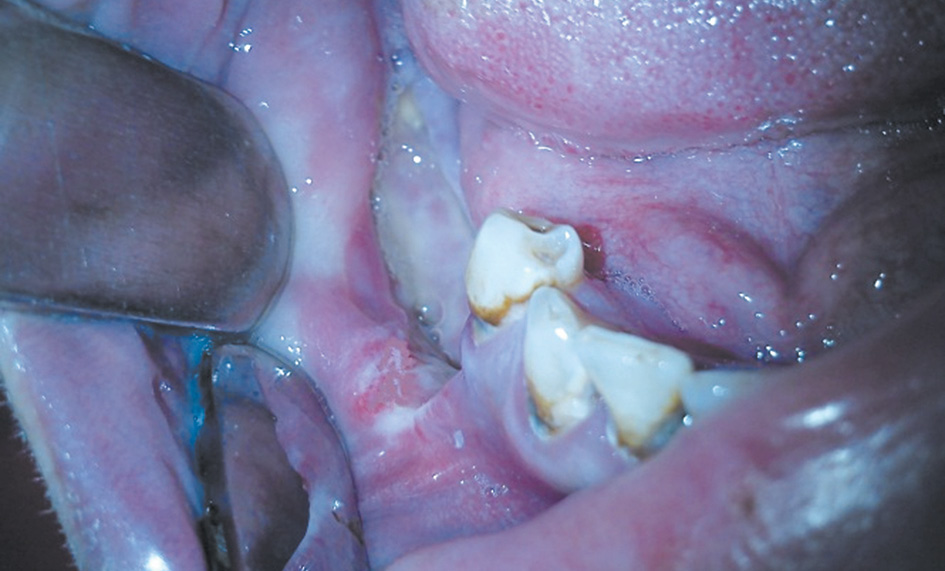

All patients from this group underwent sequestrectomy, which had characteristics that are contrary to the technique used in the treatment of odontogenic osteomyelitis. Indications for local anesthesia have been expanded due to the severe comorbidities in most patients that increase the risk of anesthetic support (chronic viral hepatitis, HIV infection in the acquired immunodeficiency syndrome stage, and chronic inflammatory lung diseases). Additional oral cavity incisions, cutting out the mucoperiosteal flaps, suturing the postoperative defects, and other manipulations that lead to oral mucosa trauma were minimized to prevent the further spread of the necrotic process. The surgical intervention involved the isolation and removal of the sequestrum, as well as the curettage of the surrounding granulation tissue. However, unlike the typical sequestrectomy technique, the mechanical treatment of the sequestral cavity walls due to bleeding and intact bone was not performed since this stage could cause a relapse and further spread of the necrotic process. The postoperative defect was plugged with iodoform turunda until healing signs of the defect by secondary intention occurred (Fig. 3).

Fig. 3. A sparing sequestrectomy. The postoperative defect is plugged with iodoformturunda / Рис. 3. Щадящая секвестрэктомия. Тампонирование послеоперационного дефекта йодоформной турундой

Thus, this technique of sequestrectomy is called sparing. The advantage of this technique includes the reduction of the risk of osteonecrosis recurrence. Further, the short-term and long-term results of surgical treatment were analyzed.

The surgery was performed in 19 patients (including 11 males and 8 females) with lower jaw osteonecrosis. They underwent a sparing sequestrectomy using the method described above. The width of the mandibular defect after sequestrectomy varied from one segment to extensive lesions including the body, angle, and ramus of the mandible. The early postoperative period was characterized by satisfactory healing, without purulent exudation, and wound healing with the formation of pink granulations in the defect area (Fig. 4).